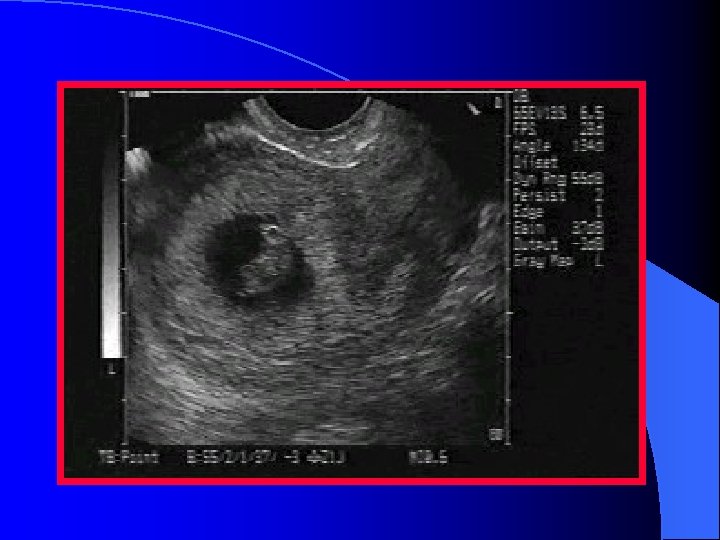

Gestational Sac l Anechoic area within the uterus surrounded by two bright echogenic rings – Decidua vera (the outer ring) – Decidua capsularis (the inner ring) l This is referred to as the double decidual sac sign (DDSS)

Definite IUP A gestational sac with a sonolucenter (greater than 5 mm diameter) l Surrounded by a thick, concentric, echogenic ring l GS contains a fetal pole or yolk sac, or both l

Empty gestational sac